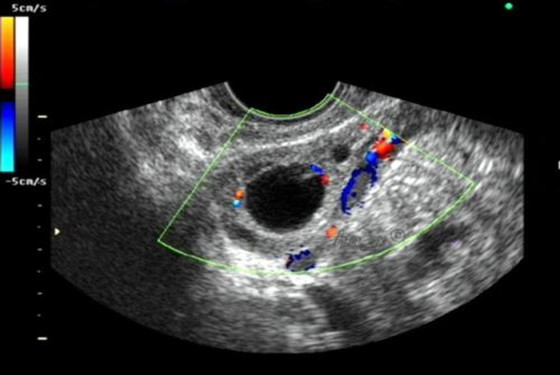

正常情况下,女性每个月月经周期都会排出一个卵子,但是也有排卵异常的情况,比如卵巢有卵泡但不排卵,导致这种情况的原因有很多,女性内分泌紊乱;子宫内膜异位症、盆腔炎;酶缺乏或前列腺素不足;卵巢功能紊乱等。